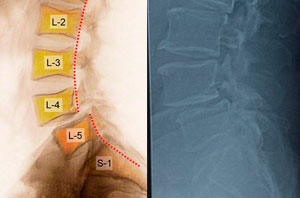

Espondilolistesis

Tengo 62 años, hace 2 años sin causa aparente comencé a sufrir de dolor de espalda bajo frecuente e intenso, y posteriormente se me adormecían, tenía calambres frecuentes y sentía pesadas las piernas. Consulte varias clínicas, hice muchas sesiones de rehabilitación, use corset, etc. sin embargo mis molestias eran cada vez más intensas. Me dijeron que tenía ESPONDILOLISTESIS L4-L5 y que debía operarme, visite varios especialistas pero ninguno me transmitía seguridad y confianza.

Mi última consulta fue con el Dr. Carlos Cárdenas el cual me explico con mucho detalle porque tenía que operarme y como era la cirugía, fue el único que se tomó el tiempo para despejar mi dudas y me hablo inclusive de eventuales complicaciones.

Tengo 18 meses Post-operado, Yo y mi familia estamos muy contentos, mis molestias desaparecieron y actualmente hago mi vida sin mayores restricciones. Muchas gracias Dr. Carlos Cárdenas.